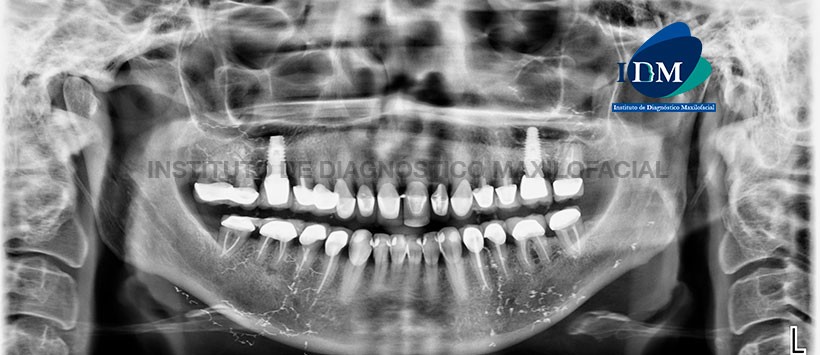

En la radiografía panorámica (Figura 1) se aprecia múltiples imágenes radiopacas de densidad metálica finas y lineales, proyectadas a nivel del maxilar superior (Senos maxilares, rebordes alveolares en zona posterior) y del maxilar inferior (zona del cuerpo mandibular y sub-mandibular).